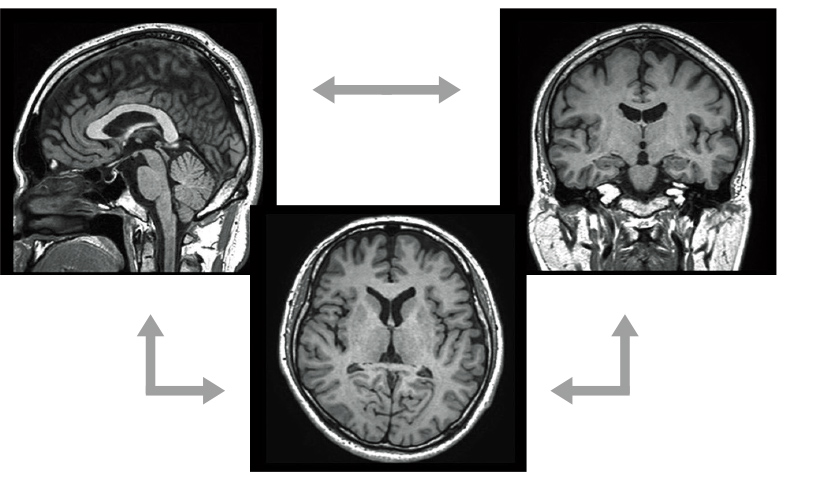

isoFSE is a high-speed 3D imaging function for isovoxels. The flip angles of refocus pulses of FSE are varied to suppress the influence from signal strength fluctuations of MultiEchoes and enable highdefinition 3D imaging. The optimization of these application patterns results in high contrasts achieved with T1WI, T2WI, and FLAIR images.

The high spatial resolution volume data acquired in imaging can be used to reconstruct images of any cross-section in MPR processing.

Reconstruction available for any cross-section